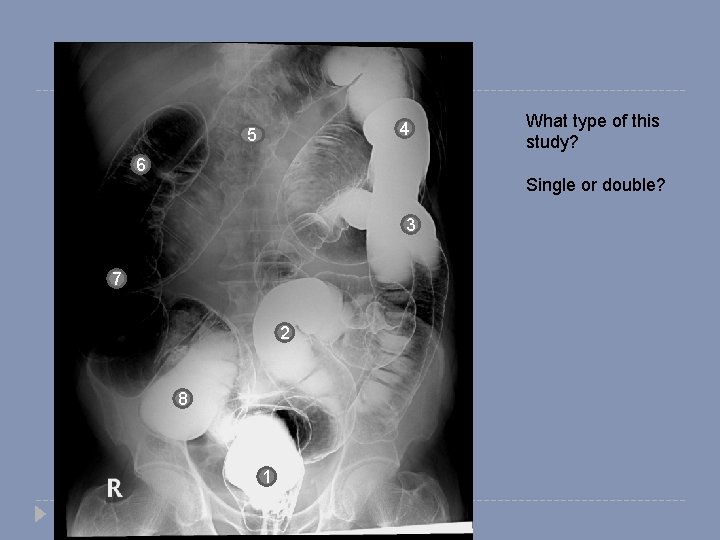

4 5 What type of this study? 6 Single or double? 3 7 2 8 1

4 5 6 1. 2. 3. 4. 5. 6. 7. 8. Rectum Sigmoid colon Descending colon Splenic flexure Transverse colon Hepatic flexure Ascending colon cecum 3 7 2 8 1